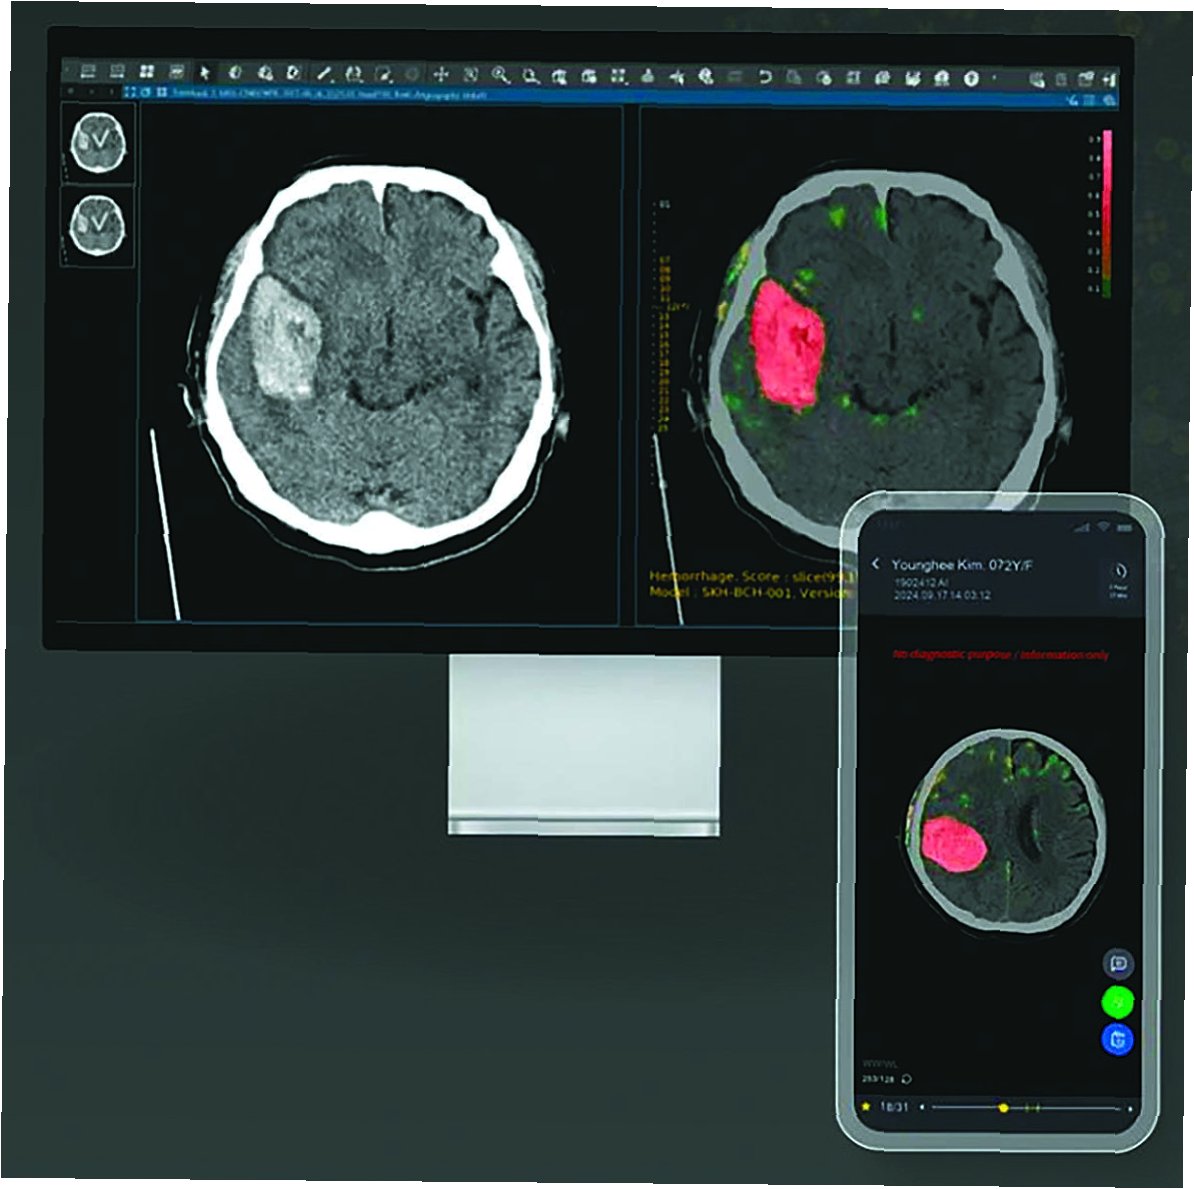

2. 정밀 진단: 뇌 영상 분석 기술을 통해 미세한 뇌출혈이나 혈관 막힘을 빠르고 정확하게 감지합니다.

전통적인 뇌졸중 진단 방법은 시간과 노력이 많이 소요되고, 전문적인 의료 지식이 필요했습니다. 하지만 AI 기술의 발전으로 뇌졸중 진단 과정은 획기적으로 변화하고 있습니다. AI는 뇌 영상 데이터를 분석하여 뇌졸중의 유형, 위치, 심각도를 빠르고 정확하게 파악합니다. 이를 통해 의료진은 더 신속하고 정확하게 진단을 내리고, 환자에게 적절한 치료법을 제공할 수 있습니다. AI 기반의 진단 시스템은 의료진의 부담을 줄이고, 뇌졸중 환자의 생존율과 예후를 개선하는 데 기여하고 있습니다.